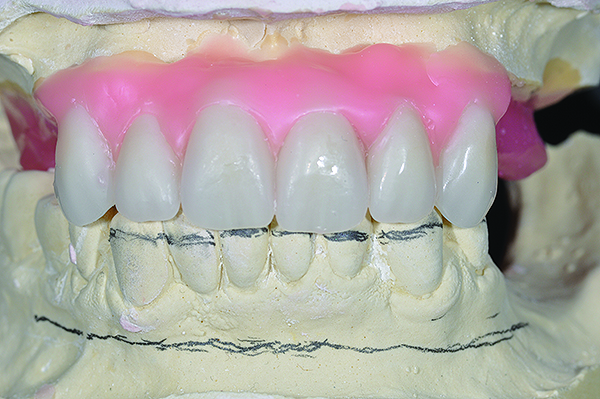

Completed diagnostic wax-up for maxillary and mandibular All-on-4 full-arch rehabilitation.

Figure 6